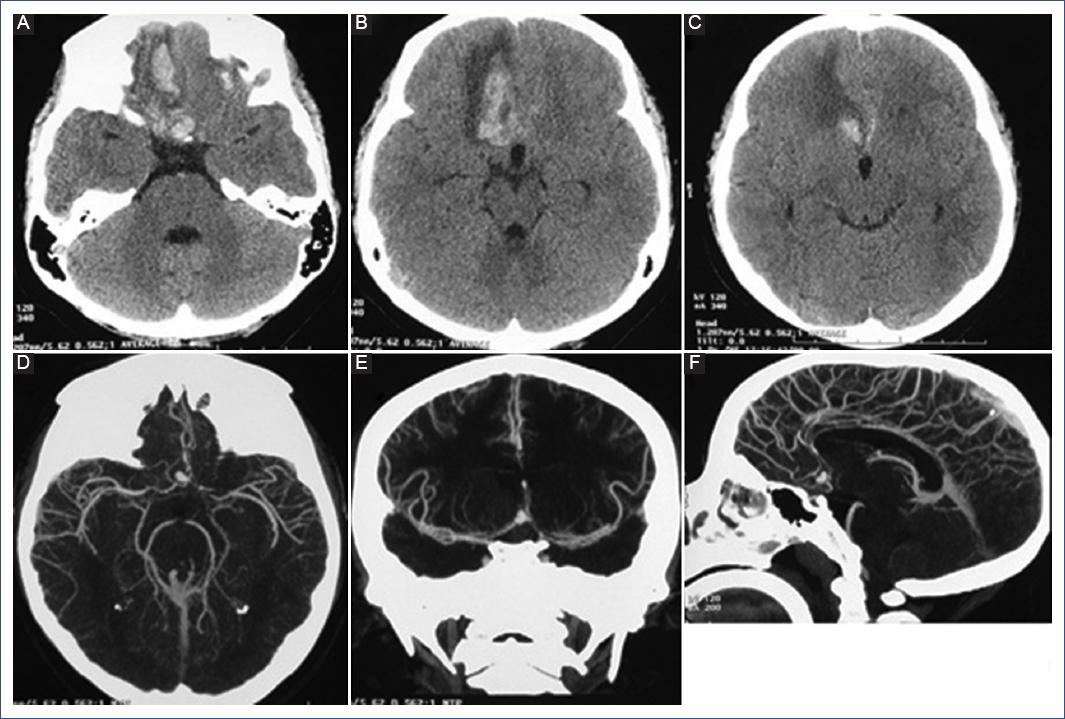

We describe the case of a 12-year-old female patient who presented with a sudden intense headache while at home and without exertion. She was initially managed with oral paracetamol at home, and after 72 hours, she developed generalized tonic-clonic seizures and was transferred to the hospital, where she was stabilized with antiepileptics and analgesics. She immediately underwent a simple cranial tomography, which showed an intraparenchymal hemorrhage within the right frontal lobe and a subarachnoid hemorrhage in the interhemispheric fissure. The study was complemented with a CTA, showing a 12 mm bilobed saccular aneurysm in the anterior communicating artery, so she was evaluated by the pediatric neurosurgeon (Figure 1).

Figure 1 A-C: Axial section of the simple cranial tomography showing a hemorrhage in the medial side of the right frontal lobe. D-F: Axial, coronal, and sagittal tomography-angiography showing bilobed aneurysm of the anterior communicating artery.